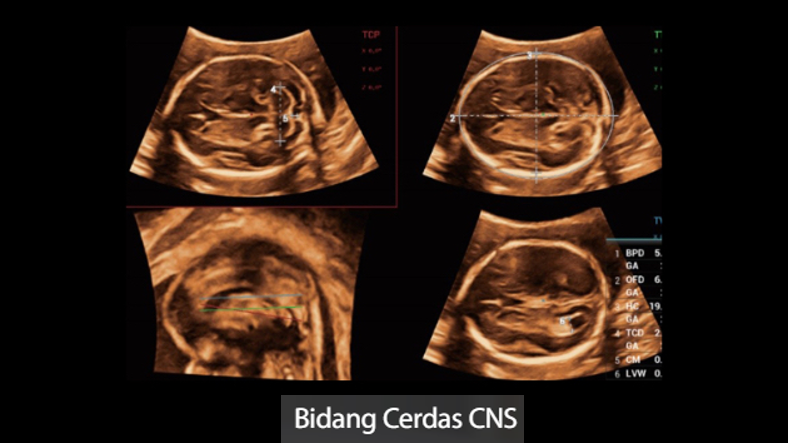

Gambar Klinis